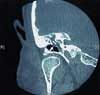

This otherwise healthy patient hasa low-grade fever, prominent submandibularlymphadenopathy on the rightside, and mastoid tenderness to palpation.Otoscopic examination reveals abulging tympanic membrane inferiorly,retraction superiorly, and a smallamount of clear serous drainage fromthe perforation in the posterosuperiorquadrant of the pars flaccida.A small, irregular mass within themiddle ear is seen through the retractedportion of the membrane. No priorimaging studies are available.The history and clinical presentationpoint to a presumptive diagnosisof a cholesteatoma. An otolaryngologistconcurs with the diagnosis, which isconfirmed by microotoscopic examinationand a CT scan of the temporalbones. The CT coronal view also showsextensive bone erosion within the middleear space (Figure 1). The CT axialview demonstrates coalescing fluid inthe right mastoid with sclerosis andhypoplasia of the air cells, which indicatesthat the fluid has occupiedthe mastoid air space for some time(Figure 2).A mastoidectomy, cholesteatomaresection, removal of the eroded headof the malleus and long process of theincus, and tympanoplasty with permanentpressure-equalization tube placementare performed. The patient toleratesthe procedure well; there are nocomplications. In 6 months, a secondsurgical procedure will be done to resectany residual or recurrent cholesteatomaand to reconstruct the middle ear byimplanting a prosthesis to partially restorethe conductive hearing loss.COMPLICATIONS OFCHOLESTEATOMASCholesteatomas often result fromchronic eustachian tube dysfunction.1The negative pressure gradient withinthe middle ear causes retraction ofthe pars flaccida of the tympanic membraneand enables the formation ofa cystic expansion of epithelial debriswith erosive properties. Over time--usually months to years--the cholesteatomaerodes the bones of the middleear and creates a hospitable environmentfor chronic otitis media.Although cholesteatomas rarelyoccur in adults, they are associatedwith life-threatening intracranialcomplications. Thus, clinicians needto maintain a high level of suspicionwhen evaluating patients with longstandingeustachian tube dysfunctionor chronic otitis media.2Bacterial meningitis. This is byfar the most common intracranial complicationof untreated cholesteatomas.A recent study demonstrated thatcholesteatomas were directly responsiblefor more than 25% of all otologicinfections that progressed to bacterialmeningitis. Of the patients with cholesteatomasand bacterial meningitis,41% had a history of corrective surgeryfor their chronic ear condition.Despite aggressive medical and surgicaltreatment, between 5% and 10% ofpatients in the study died of otogenicbacterial meningitis.3Brain abscess and epiduralempyema. These conditions aremore serious intracranial sequelae ofuntreated cholesteatomas. Cholesteatomasare responsible for mostof the brain abscesses and epiduralempyemas that result from untreatedotologic disease (from 59% to morethan 95% in various studies).4-6 Despiteundergoing aggressive medicaland surgical treatment, 10% of patientswith otologic infection-inducedbrain abscesses and epidural empyemasdie of these conditions.5TREATMENTWhen a cholesteatoma is suspected,immediate consultation with anotolaryngologist and a CT scan of thetemporal bones are warranted. Thescan can also be used to determinethe extent of the cholesteatoma and toidentify the location of critical surgicallandmarks before the operationSurgical interventions includemastoidectomy, resection of thecholesteatoma, and tympanoplastywith permanent pressure-equalizationtube placement. Once the diagnosisis confirmed, most procedures canbe done on an elective basis; however,emergency surgery is indicatedwhen: